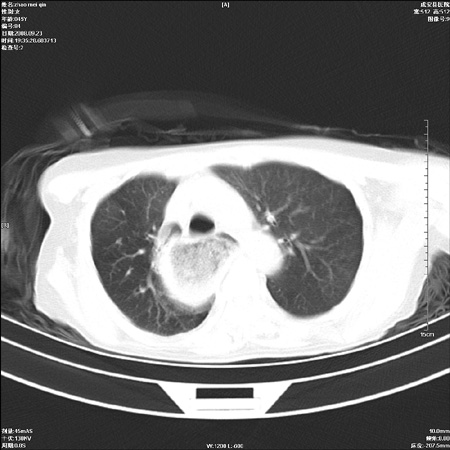

标题: CT15861:女 60 外伤后1小时 胸疼 [打印本页]

标题: CT15861:女 60 外伤后1小时 胸疼

外伤后1小时 胸疼 是外伤后引起的吗?

食道ca术后胸腔胃,右肺挫伤?

非外伤性改变,典型的贲门失迟缓症

食道扩张明显下端逐渐变窄,大量食物存留,象贲门失迟缓症。